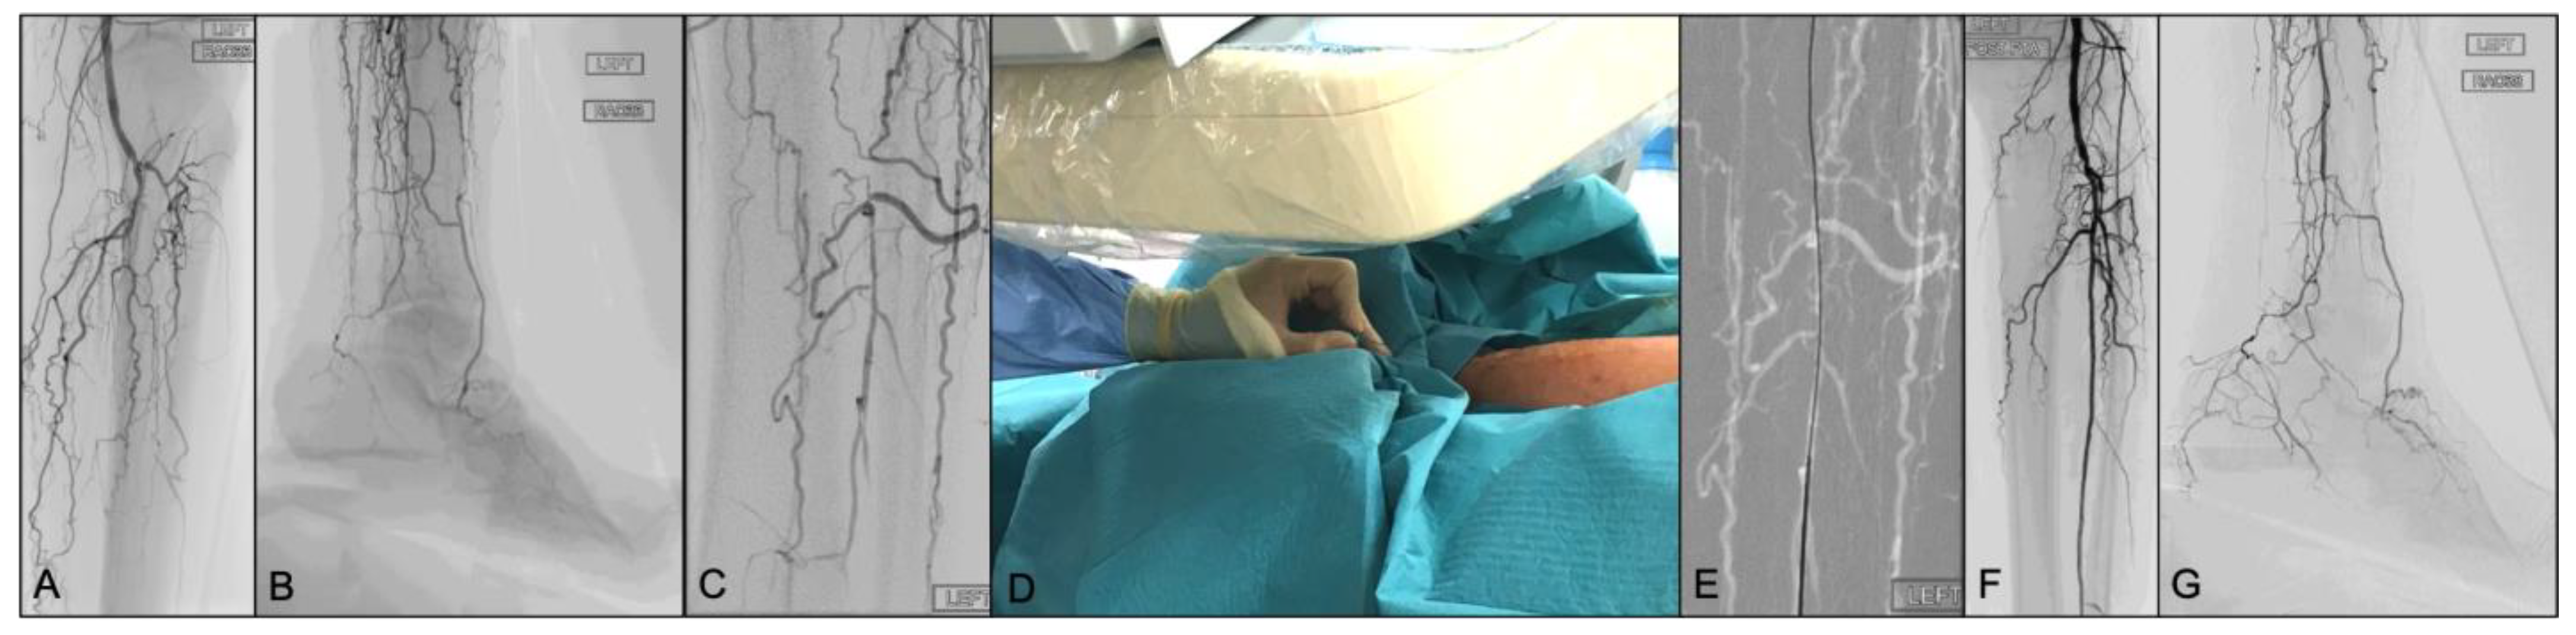

With regards to the retrograde peroneal puncture, we used the distal popliteal/tibio-peroneal trunk puncture technique, using fluoroscopic guidance, independently described by Silvestro et al. [33] and Tan et al. [34] in 2018. However, we would like to focus on the following key points (illustrated in Figure 1 and Figure 2), which are specifically important for peroneal artery punctures:

Figure 1.

Rutherford 6 CLTI patient with no patent arterial vessel reaching the left forefoot. Peroneal artery is occluded few centimetres below its origin with distal reconstitution of the vessel just above its anterior and posterior branches division (A,B). After a failed antegrade recanalization attempt, the distal peroneal artery was visualized under fluoroscopic guidance (C) in the 25-degree left anterior oblique (LAO) position to visualize the artery between the fibula and tibia. A 21-gauge needle (7 cm) was advanced with an angle of approximately 45 degrees (D), aligned straight with the vessel smart-mask. A 0.018 wire was introduced through the needle, once bleeding was controlled (E). The final result after intraluminal recanalization subsequent angioplasty, with direct flow reaching the forefoot via the reconstituted peroneal artery (F,G).